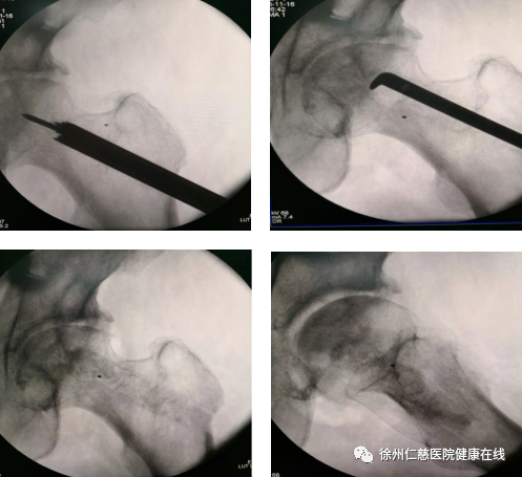

天玑机器人对髋关节精准定位、精准钻孔

钻孔减压术可以减轻股骨头颈内高压,改善血液循环,减轻骨髓水肿,阻止股骨头坏死的进一步发展。在天玑机器人辅助下,精准定位聚焦病灶,通过骨科机器人机械臂的引导,将导针准确打入坏死病灶进行减压,这样能有效改善股骨头内部的血液循环。钻孔减压+体外冲击波+激光磁综合治疗股骨头坏死,创伤较小、切口小,手术风险小、并发症少。

34岁男性患者,因“双髋关节疼痛伴活动受限33天”入院。双髓关节正位片示:双侧股骨头稍变扁,密度不均,双侧髋骨质增生改变、密度增高,髋关节间隙稍窄、不等宽,诊断双侧股骨头缺血性坏死(II期) 。